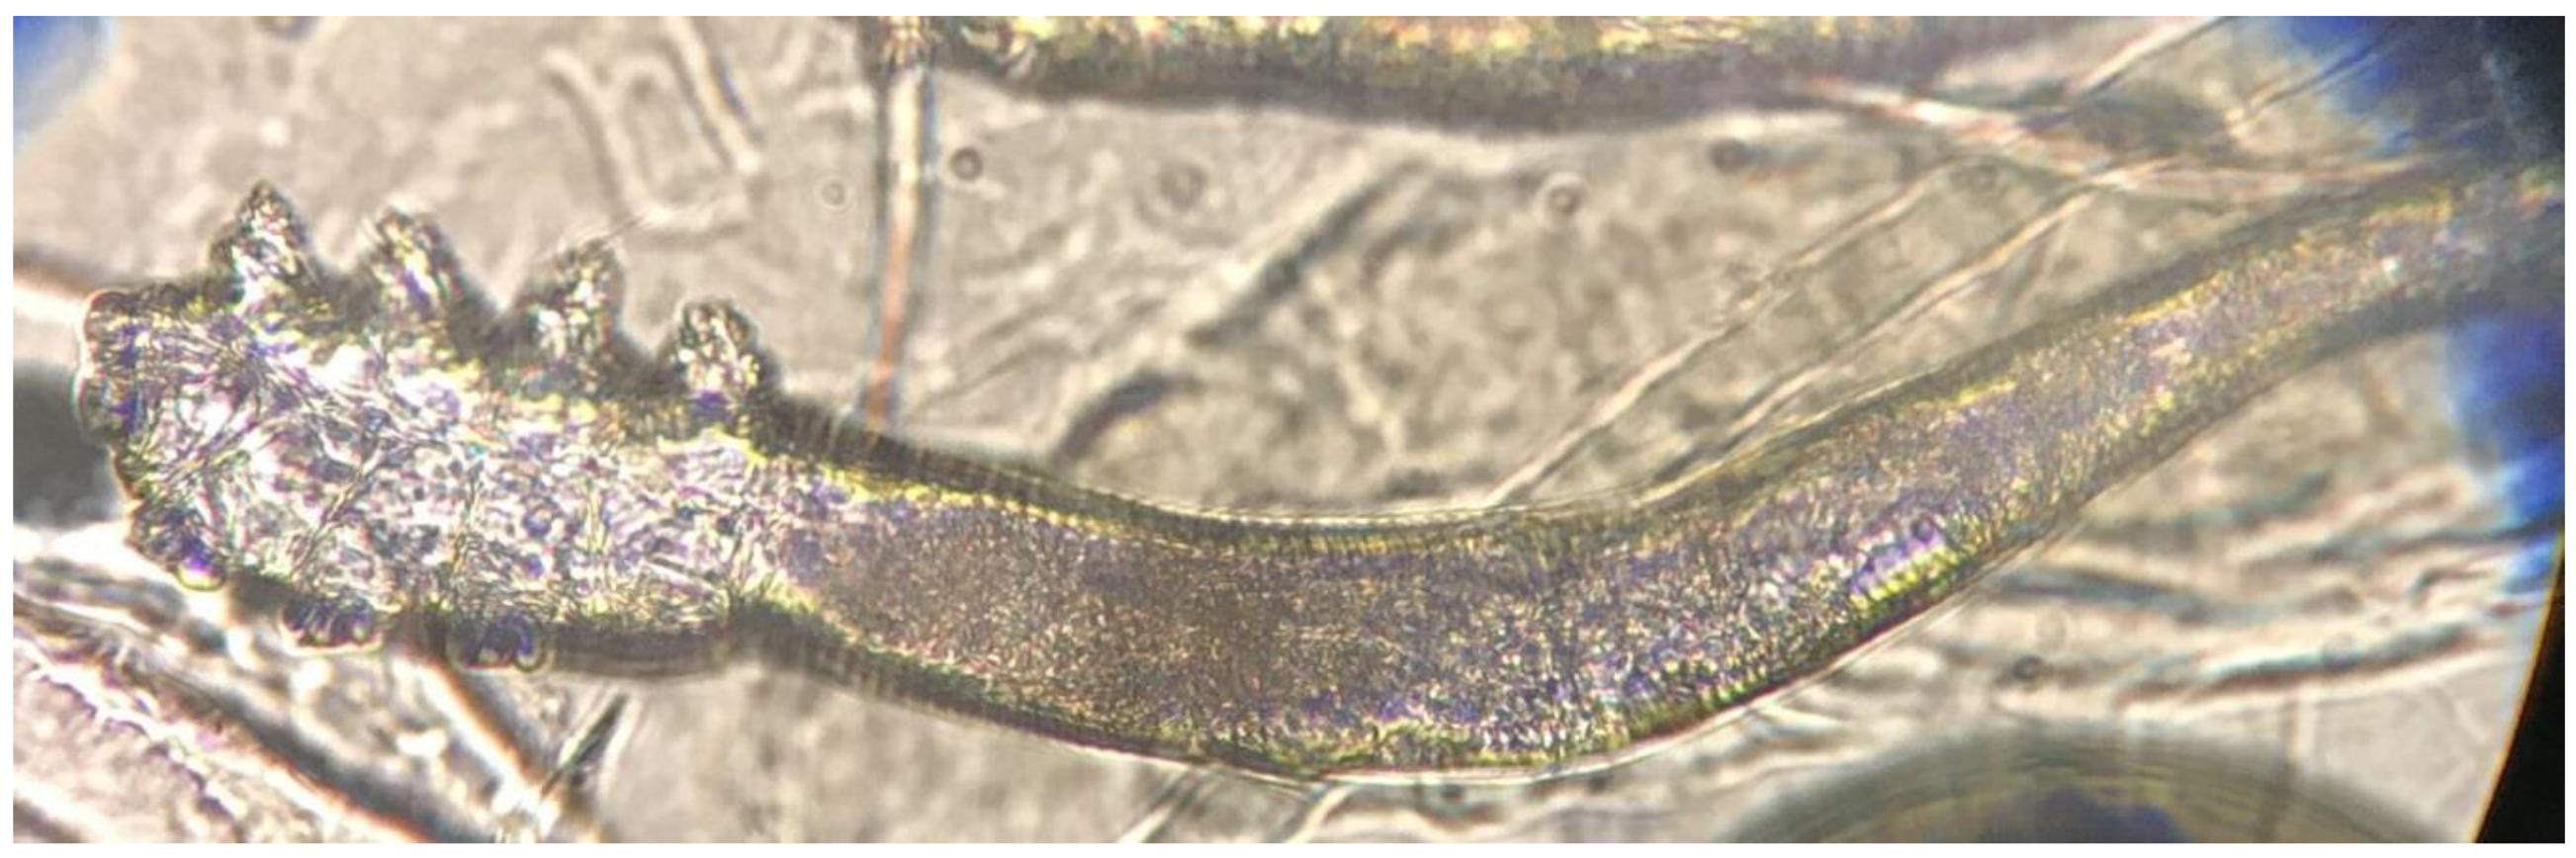

The Demodex test was performed in both heart failure and age and sex-matched control groups. At least one Demodex mite was detected in 20 (56%) out of 36 HF patients and nine (25%) of control group (p = 0.008). (Figure 1 and Figure 2) The number of Demodex mites detected was significantly higher in the HF group (median 1; min. 0 and max. 10) compared to the control group (median 0; min. 0 and max. 3) (p < 0.001). Demodicidosis, which is defined as the determination of five or more Demodex mites in a 1-cm2 area, was positive in 14 (40%) HF patients. In none of the controls was demodicidosis detected (p < 0.001) (Table 2).

Figure 1.

Single Demodex mite on standardized skin surface biopsies (SSSBs) under ×40 magnification by light microscope.

Figure 2.

Demodex mite on SSSBs under ×40 magnification by light microscope.